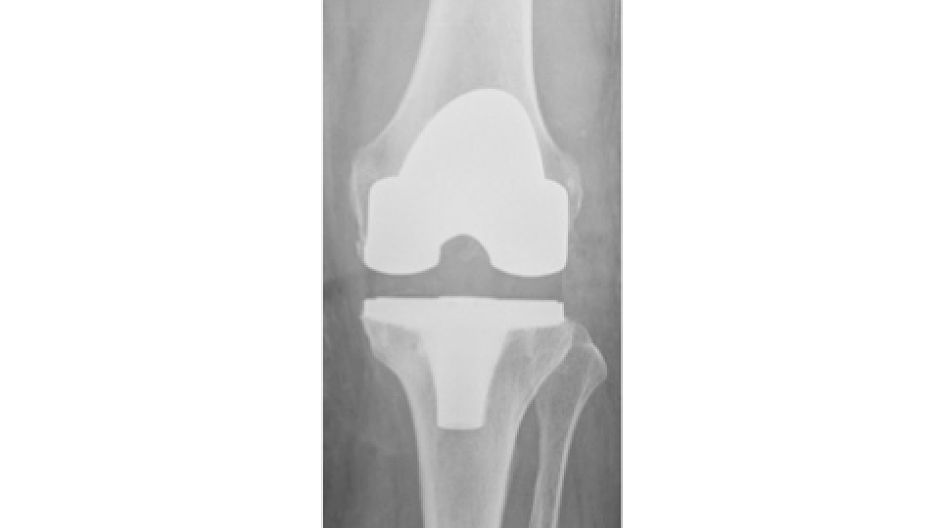

Fotos Unfallchirurgie und Orthopädie